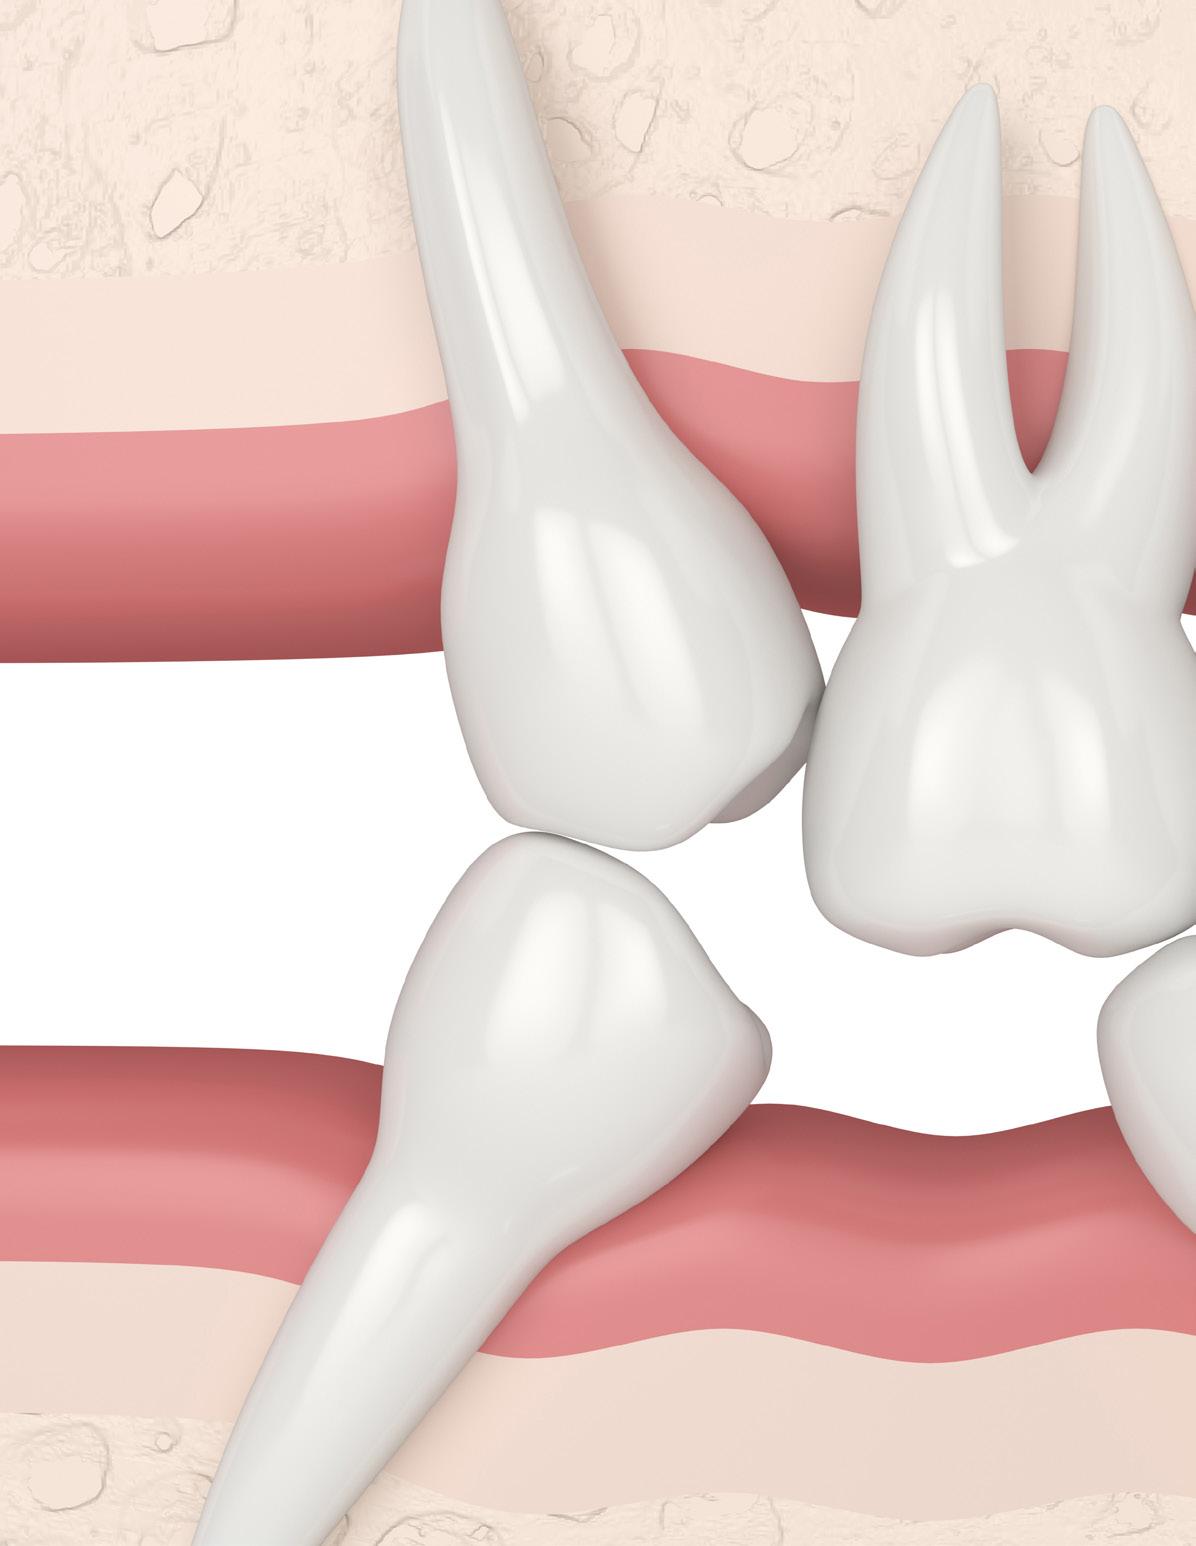

En el inicio del uso de estos aditamentos (TAD) se utilizaban con frecuencia los microtornillos intraalveolares que se colocan entre las raíces de los dientes entre otras localizaciones. Hoy en día se siguen utilizando, pero con la aparición de los microtornillos extraalveolares se reducen sus indicaciones, es decir, cada vez se emplean más porque presentan más ventajas en comparación con los interradiculares.1,2 Los microtornillos extraalveolares no solo resuelven el problema de anclaje sino que también consiguen tratar casos de extracciones sin tener que realizarlas gracias a la biomecánica que permiten.1,3 Se requieren microtornillos de mayor diámetro y longitud que los microtornillos interradiculares, entre 1.5 y 2 mm de diámetro y de 10 a 17 mm de longitud, en cambio los microtornillos interradiculares presentan un diámetro menor de 1 y 1.5 mm y longitud de 6 a 8 mm. Los

microtornillos extraalveolares están indicados para corregir una amplia variedad de maloclusiones complejas, en cambio los microtornillos interradiculares están indicados para corregir problemas concretos como: mesialización molar unilateral o bilateral, intrusión de incisivos y corrección de un plano oclusal asimétrico.2

Los microtornillos extraalveolares presentan una serie de ventajas frente a los interradiculares: menor riesgo de lesión de las raíces y ligamento periodontal, anclaje adecuado debido a una mayor cantidad de hueso cortical, tasa de fracaso mucho menor, inflamación de las encías en zonas no visibles, posibilidad de tratar casos complejos y con menor número de microtornillos, aplicación de fuerzas con vectores múltiples, modificación del plano oclusal e incisal, posición bucal de la cabeza del microtornillo que permite una correcta biomecánica, además de presentar mayor diámetro y longitud lo que favorece la estabilidad primaria.1,4,5,6